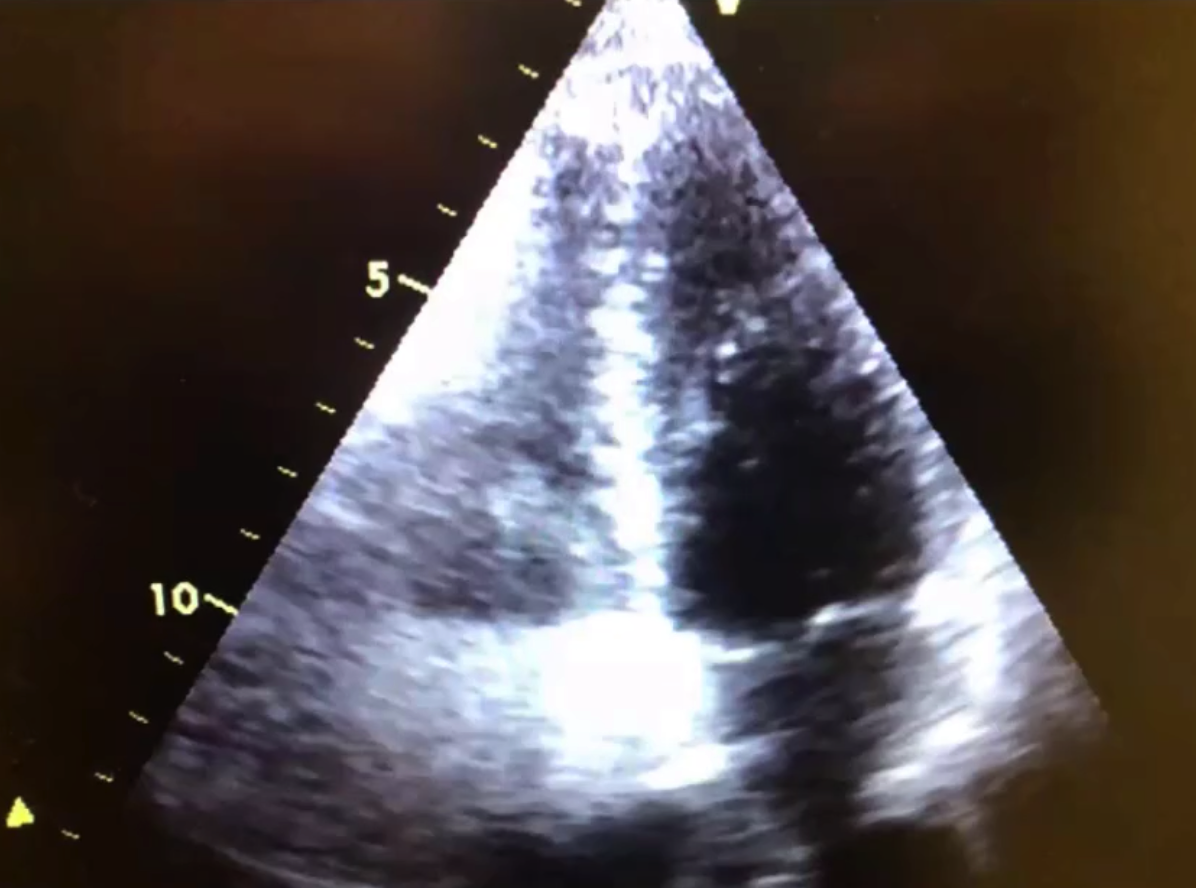

It delineates the endocardium, making it very easy to see difficult features

它描绘了心内膜,不易观察到的部分变得很容易看到- Typical example: The lateral wall of the LV can be difficult to see in both the Short axis and the 4 Chamber view

典型例子:左室的侧壁在短轴和四腔观中都很难看到 - The use of contrast resolves that issue.

使用对比剂可以解决这个问题

LV thrombi (clots) can be difficult to distinguish from artefact.

左室血栓 (血栓) 可能很难与伪像相区别- Ultrasound harmonics can create shadows in the image. These can sometimes look like clot.

超声谐波成像技术,会在图像中产生阴影。这些有时看起来像凝块。 - The use of contrast eliminates this.

使用对比剂可以剔除

Excellent for use in LV volume and function by delineating the endocardium, thus making calculations more accurate.

通过描绘心内膜,非常适合用于左室容积和功能的评估,使计算更加准确。![]()

- Power Doppler image recorded at the time of contrast echocardiography using a perfluorocarbon-based agent. Note the excellent signal-to-noise ratio and the marked discrimination between the blood pool and the wall with this imaging method.

使用基于全氟化碳的试剂进行对比超声心动图时记录的功率多普勒图像。注意这种成像方法的出色信噪比和血池与血管壁之间的明显区别。